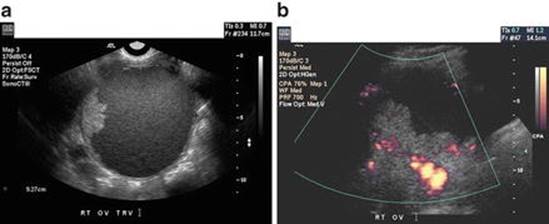

Ovarian Malignancy

Features of malignant masses on transvaginal ultrasound include papillary projections , thick septations (>3 mm), and solid components with color Doppler flow (Fig. 4.15) [62, 74]. The presence of ascites is also highly concerning for malignancy, though ascites may also be identified in benign conditions as well, such as ovarian fibromas and OHSS [75]. CT scan may also be useful in characterizing pelvic masses concerning for malignancy by detecting metastatic disease and peritoneal carcinomatosis.

Fig. 4.15

Ovarian cancer. (a) A solid excrescence is present on the inner cyst wall of this complex ovarian cyst. (b) Doppler examination of the mass reveals multiple intermediate resistance vessels. A stage I-C epithelial ovarian cancer was found at laparotomy (Reprinted from Cohen [62], Figure. 4a, b, with kind permission from Springer Science and Business Media)